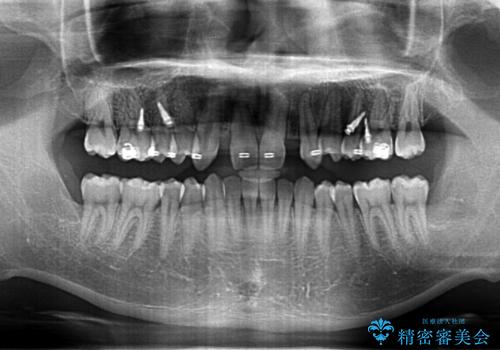

前歯のすきま 生まれつき歯が少ないのを治療

- 前歯の隙間を気にして来院。

生まれつき上の歯が二本少ない状態でした。

バラバラに位置している前歯の位置を矯正治療で修正してからブリッジを装着しています。

また、全体矯正もご希望でしたので下の歯のがたつきや、すれ違っているかみ合わせも治療しています。

矯正治療によって事前に歯の位置を修正しているため、ダミーの歯の大きさも調整し、自然な仕上がりにしました。また、犬歯のねじれを治してから削っているため、神経をとらずに歯の形を整えることができました。

親知らずは矯正前に抜歯しています。